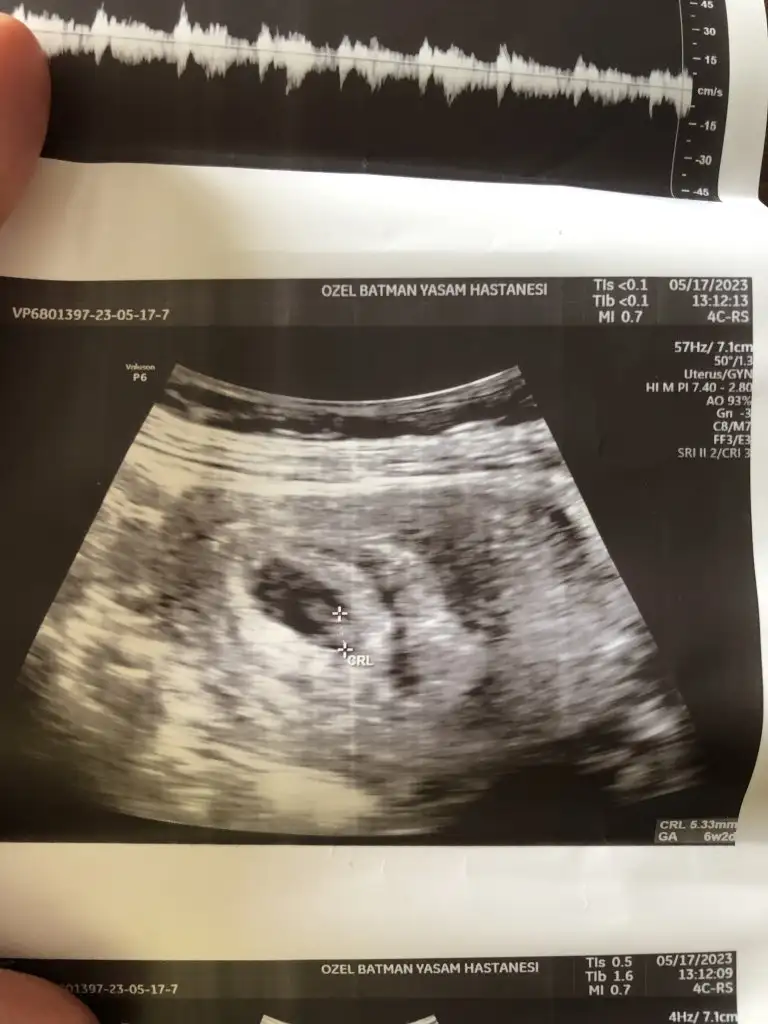

bugün kontrole gittim 6+3 olmuşuz herşey iyi dedi kalbini duyduk ama kanama alanı var dedi korkma bebeğin gelişmeye çalıştığını gösterir dedi melegim can melegim can cinsiyet tahmini alabilir miyim 😊

Eklentiler

• 61E97CE4-0F58-430E-B828-44C952EB5BEA.webp

61E97CE4-0F58-430E-B828-44C952EB5BEA.webp

34,5 KB · Görüntüleme: 56